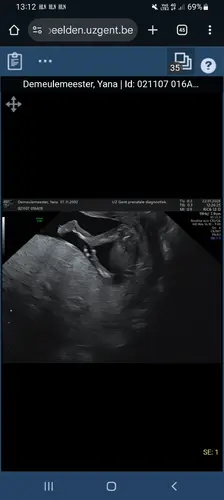

Vandaag de 12 weken echo laten doen! Ons spruitje meet 6,82cm. Nu de nipt spannend afwachten ahhh 🤭 neusbeentje is aanwezig en ook de nekplooi zag er oke uit dus we zijn weer even gerustgesteld 🥹